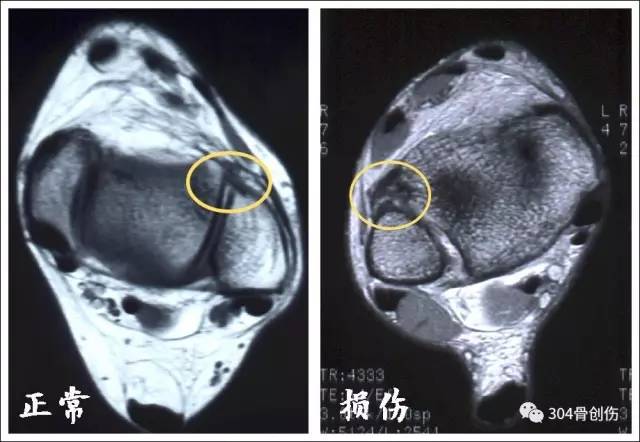

MRI 诊断

MRI能够直观看到下胫腓韧带损伤,敏感度较强,量化评价下胫腓分离逊于CT三维重建,一般CT检查足以诊断下胫腓分离,不必常规再行MRI检查,能更好节约医疗费用。

下胫腓前韧带对比

骨间韧带对比

骨间膜对比

下胫腓后韧带对比